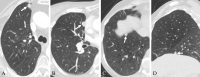

Background Pulmonary noncalcified nodules (NCNs) attached to the fissural or costal pleura with smooth margins and triangular or lentiform, oval, or semicircular (LOS) shapes at low-dose CT are recommended for annual follow-up instead of immediate workup. Purpose To determine whether management of mediastinal or diaphragmatic pleura-attached NCNs (M/DP-NCNs) with the same features as fissural or costal pleura-attached NCNs at low-dose CT can follow the same recommendations. Materials and Methods This retrospective study reviewed chest CT examinations in participants from two databases. Group A included 1451 participants who had lung cancer that was first present as a solid nodule with an average diameter of 3.0-30.0 mm. Group B included 345 consecutive participants from a lung cancer screening program who had at least one solid nodule with a diameter of 3.0-30.0 mm at baseline CT and underwent at least three follow-up CT examinations. Radiologists reviewed CT images to identify solid M/DP-NCNs, defined as nodules 0 mm in distance from the mediastinal or diaphragmatic pleura, and recorded average diameter, margin, and shape. General descriptive statistics were used. Results Among the 1451 participants with lung cancer in group A, 163 participants (median age, 68 years [IQR, 61.5-75.0 years]; 92 male participants) had 164 malignant M/DP-NCNs 3.0-30.0 mm in average diameter. None of the 164 malignant M/DP-NCNs had smooth margins and triangular or LOS shapes (upper limit of 95% CI of proportion, 0.02). Among the 345 consecutive screening participants in group B, 146 participants (median age, 65 years [IQR, 59-71 years]; 81 female participants) had 240 M/DP-NCNs with average diameter 3.0-30.0 mm. None of the M/DP-NCNs with smooth margins and triangular or LOS shapes were malignant after a median follow-up of 57.8 months (IQR, 46.3-68.1 months). Conclusion For solid M/DP-NCNs with smooth margins and triangular or LOS shapes at low-dose CT, the risk of lung cancer is extremely low, which supports the recommendation of Lung Imaging Reporting and Data System version 2022 for annual follow-up instead of immediate workup. © RSNA, 2024 See also the editorial by Goodman and Baruah in this issue.